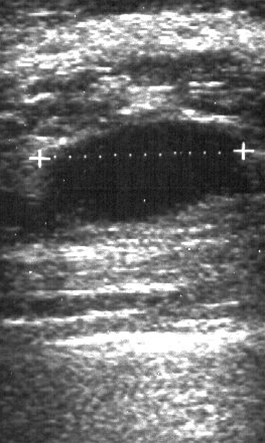

En cyste i brystkirtlen viser sig som en ekkofri velafgrænset oval struktur.